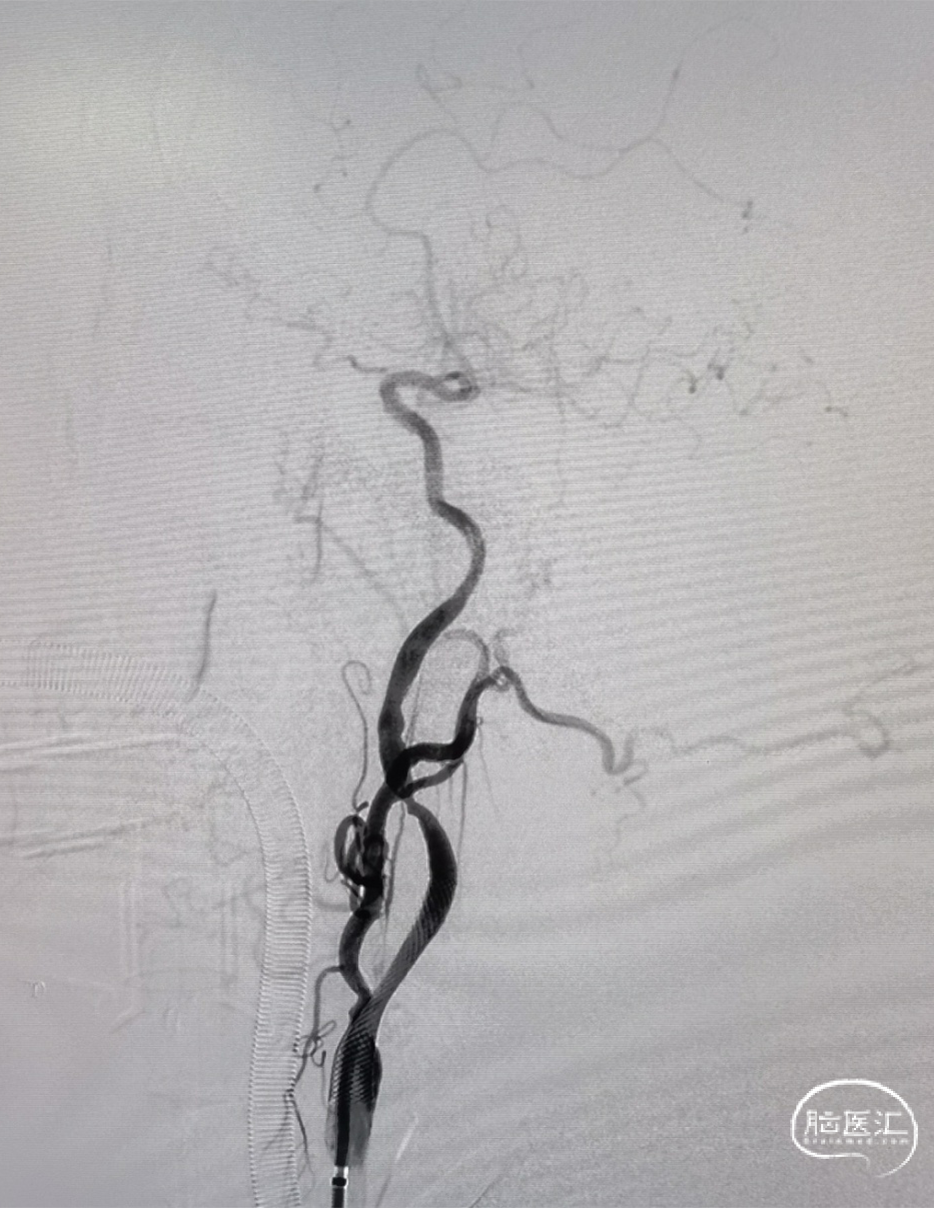

4*30mm Syphonet®取栓支架释放后路图。

大脑前动脉第一次取栓后路图,血管仍闭塞,且长鞘掉到颈总。

再次超选发现颈内动脉起始部重度狭窄伴夹层。

再次超选并将Syphonet®取栓支架释放后造影见血流通畅,回收取栓支架后血管再次闭塞,遂将4.5*28mm 支架置于大脑前动脉释放,支架释放后造影血流恢复满意。